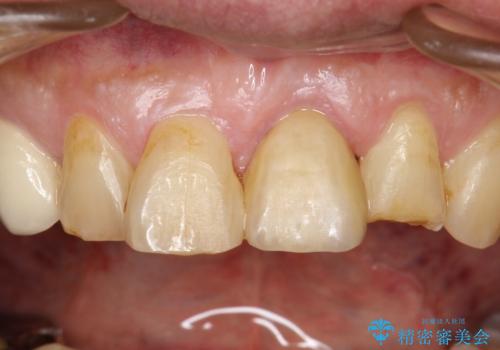

とても治療に対しての意識が高い方で、最初のころは歯磨きもあまりできていませんでしたが、衛生士さんの指導もあり、治療を進めるうちにプラークコントロールも改善していました。

歯を引っ張りあげたり、手術をしたあとの治り待ちをしたり、治療に時間がかかる方法ではありましたが、抜かずにその歯を使うことができたことで、患者さんにはとても満足していただけています。